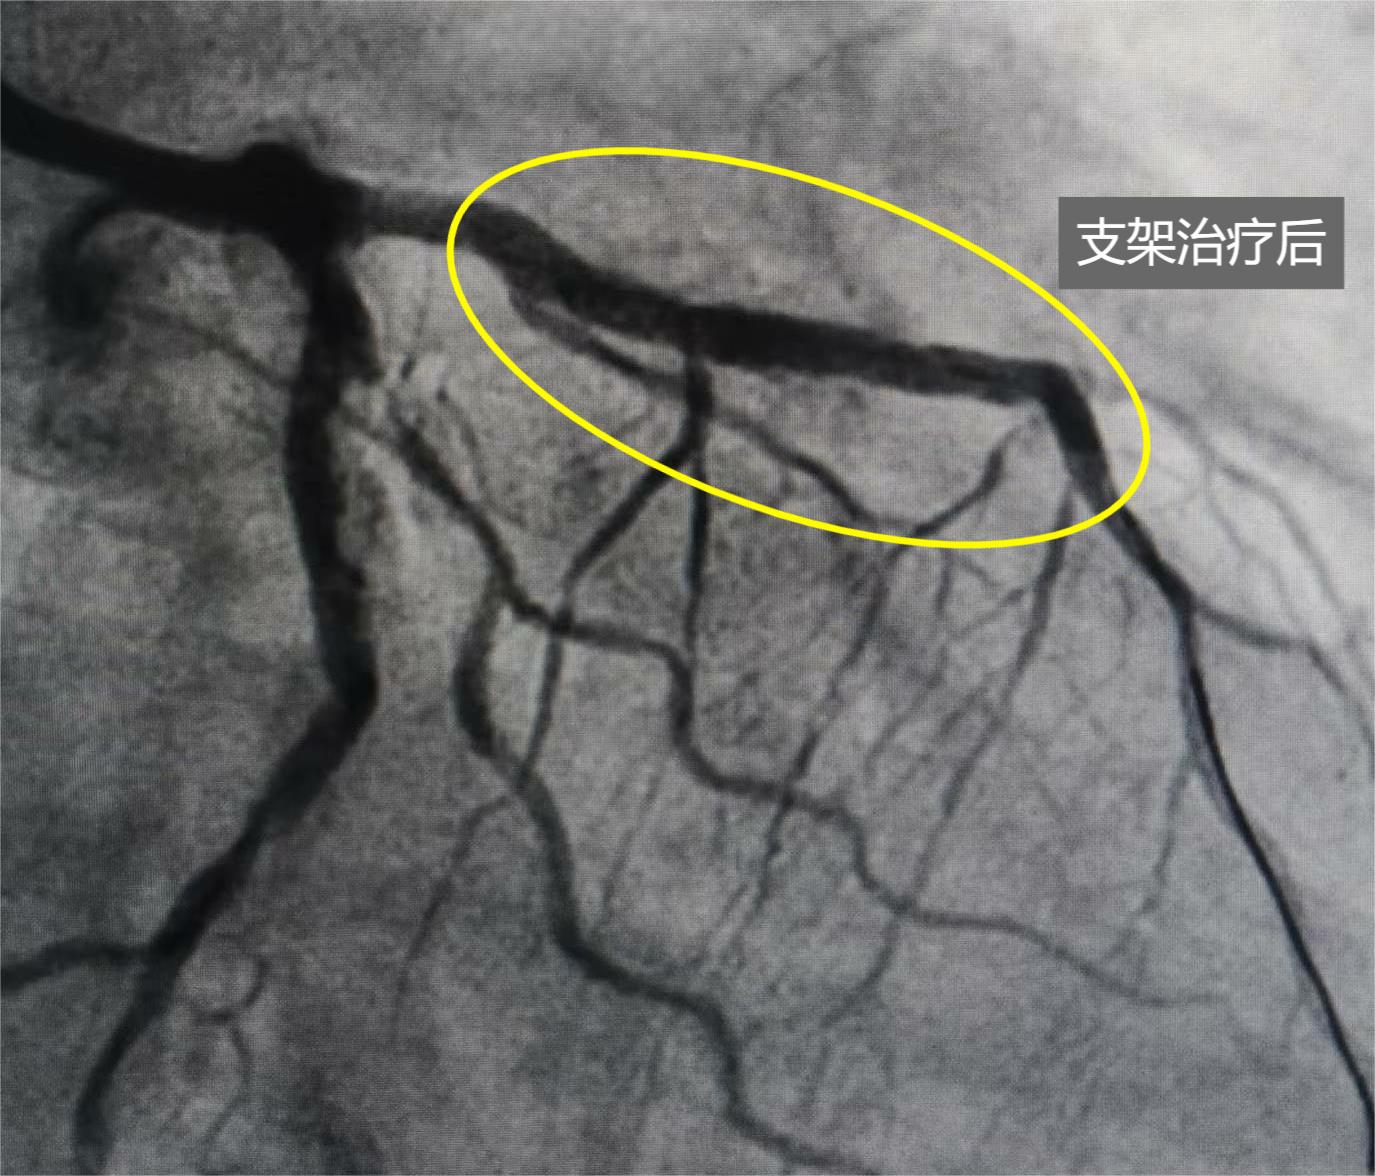

馬老先生旋磨后植入心臟支架的前降支血管,恢復理想。

5月6日中午,歷經兩個多小時的手術,在衡水市人民醫院(哈勵遜國際和平醫院)心內科負責人張慧晶指導下,副主任醫師肖建東博士利用精湛技術操控旋磨導絲及旋磨頭,對馬老先生前降支鈣化病變進行了“冠狀動脈內旋磨術”處理:在面積僅有7平方毫米左右的心臟血管里,用微導管輔助交換旋磨導絲至心臟前降支遠端,用一枚直徑1.75毫米的旋磨頭,以每分鐘16萬轉的速度高速旋磨,將重度鈣化病變處一點點磨掉,然后再用球囊充分擴張前降支病變處,并成功植入兩個支架,打通了馬老先生的“生命通道”。在推出手術室后,馬老先生用舒展的笑容,表達了此刻滿滿的幸福。